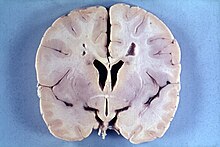

Hydranencephaly-dilated third ventricle (V) with absent thalami and basal ganglia and cerebral cortex